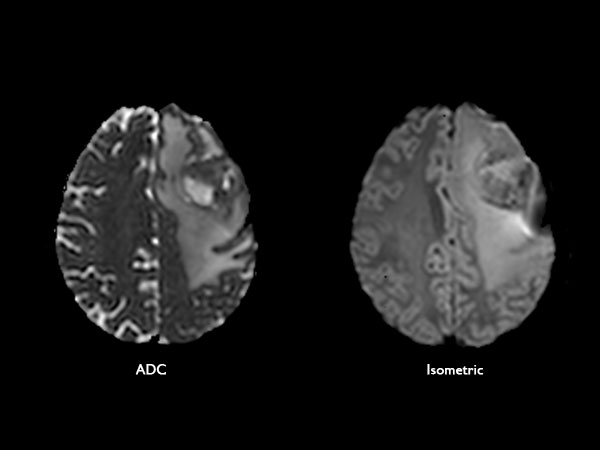

Axial Diffusion Tensor Imaging (15 directions)